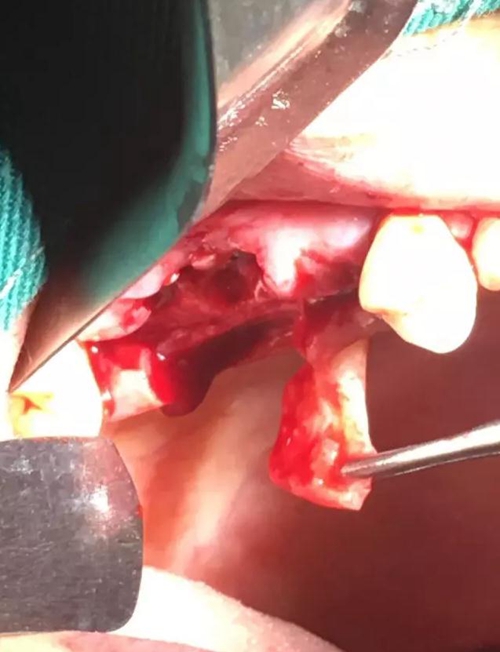

【病例分享】內(nèi)提,用自體骨柱,不用骨粉

5.jpg